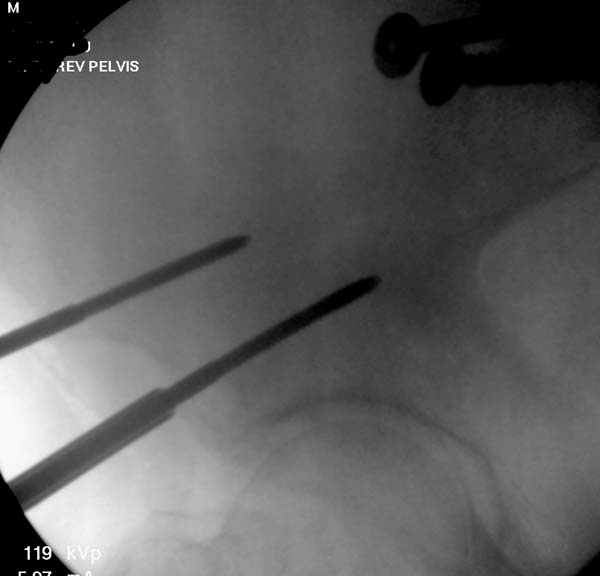

Большое спасибо всем Вам за помощь! Вчера прооперировали пациентку. Выполнили закрытую репозицию левой половины таза на тракционном столе под контролем ЭОП, закрытая фиксация левого КПС двумя каннулированными винтами. Учитывая удовлетворительное стояние отломков лонной и седалищной костей справа, а так же удовлетворительную ширину лона передние отделы стабилизировали системой ЦИТО

Послеоперационные КТ прилагаются

Винты введены в S1

Здесь снимки, которые показывают направление стержня, а также идею репозиции вытяжением. На рентгенопроницаемых столах имеется возможность установить дополнительную раму, где по желанию можно увеличить или уменьшить высоту угла вытяжения. Для репозиции таза больной в положение на спине, стержень для вытяжения остается во время операции. Система подойдет для тракции головки бедра из вертлужной впадины, и для этого стерильная веревка и Synthes Universal Chuck with T-Handle.

Двухстороннее повреждение крестца и травматическая ампутация бедра, где неопытной бригадой дежурантов установлен верхний наружный фиксатор для стабилизации. На третий день ревизия на более стабильный, и окончательная фиксация. Первые снимки после стабилизации таза, и другие, где показаны (параллельные) правильная установка на AIIS т.е на месте прикрепления прямой мышцы бедра. Ампутация закончена костно пластическим методом.